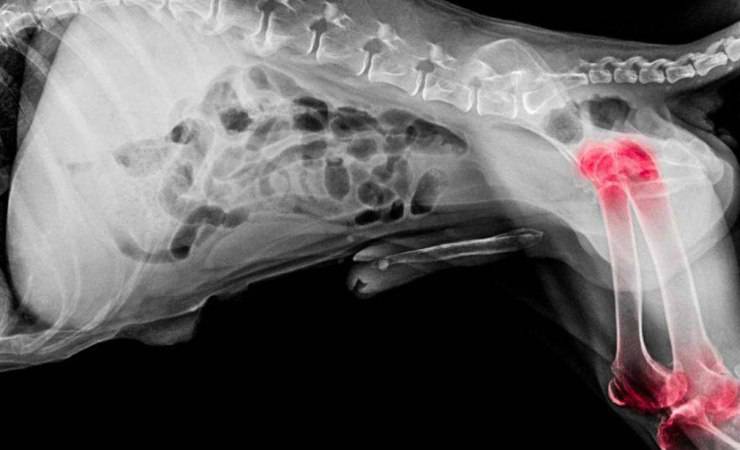

Displasia dell’anca

La displasia dell’anca nel Cane da pastore dei Pirenei a faccia rasa, è una patologia ereditaria perciò si tratta di soggetti geneticamente predisposti.

Si verifica quando il femore non va sa posizionarsi nel modo corretto nella cavità dell’anca dell’animale.

Esistono, diversi gradi di questa malattia che possono essere più o meno gravi.

Nei casi più gravi di displasia all’anca canina, può verificarsi fin da cucciolo oppure manifestarsi nell’età adulta avanzata quando si hanno casi più lievi.

Questa problematica, crea come conseguenza un andamento zoppicante e dolore intenso nel cane.

Altri segnali che si possono manifestare variano molto in funzione dell’età del cane, dello stadio di avanzamento della malattia e della limitazione del funzionamento dell’articolazione.

Per la cura della displasia dell’anca nel cane, esistono diverse terapie ma il trattamento più estremo richiede un intervento chirurgico.